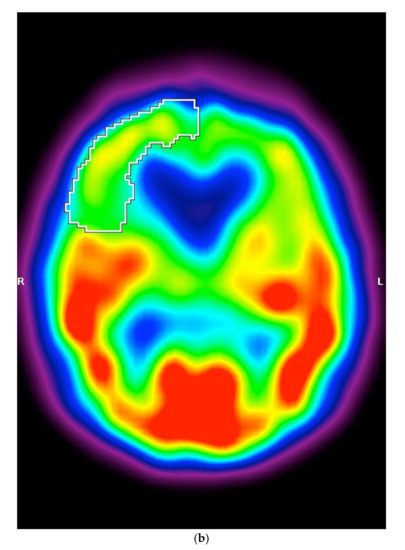

In SPECT imaging, patients with MSA-P had higher regional cerebral blood flow in the right frontal lobe (p = 0.0012) (Figure 2a–c).

Figure 2.

(a) Scatterplot presenting the significant differences between MSA-P and PSP-P in the right frontal lobe, (b) Axial 99mTc-HMPAO SPECT of a patient with PSP-P (frontal lobe hypoperfusion), (c) Axial 99mTc-HMPAO SPECT of a patient with MSA-P (without frontal lobe hypoperfusion).